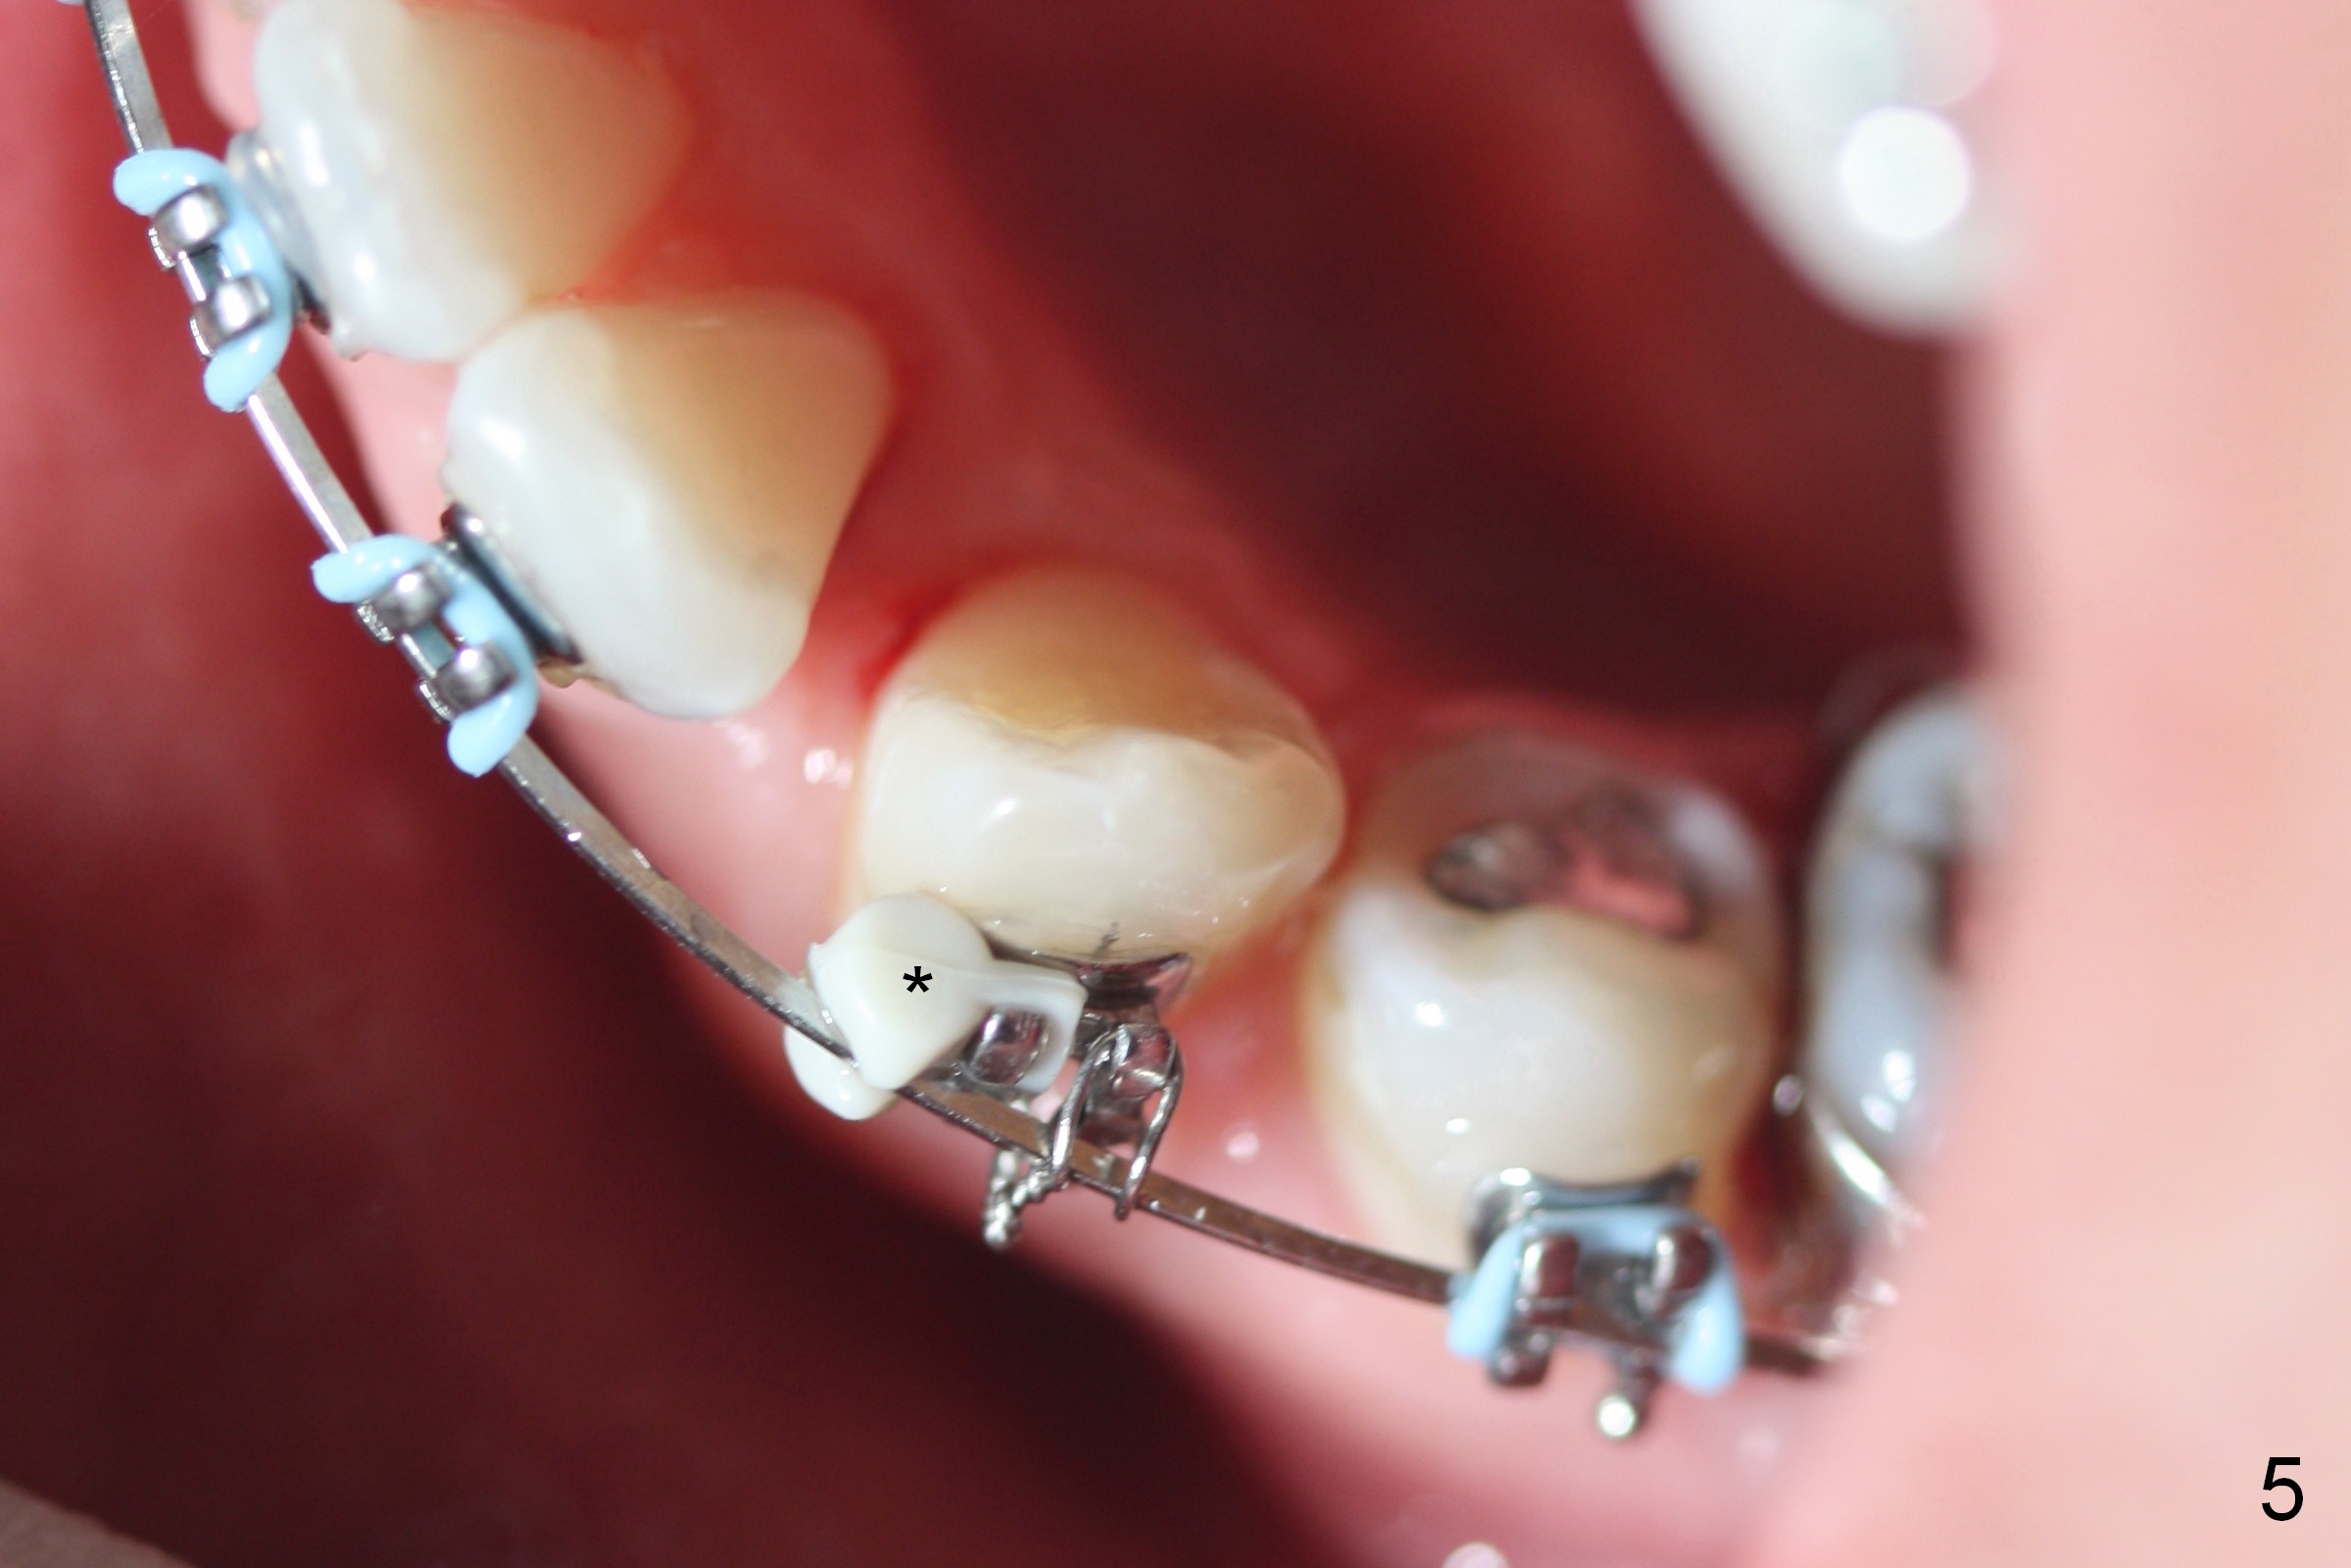

LR4 (Fig.1) and LL3 (Fig.2,3) are distalized 7.5 months of ortho treatment (1,2). Next step is to retract LR3 with closed coil spring (Fig.4) and de-rotate LL3 with a rotation wedge (Fig.5 *). The upper arch appears to be slightly in cross bite (Fig.4) 2 months after closed coil springs placed between the upper posted wire (<) and mini-implants (placed in the buccal tuberosity). Profile needs to be improved (Fig.6,7).

LR 3 shows no sign of distalization the 1st month after placed under closed coil spring (Fig.8), but obvious change occurs the 2nd months (Fig.9,10). Without closed coil spring, LL3 rotation (Fig.5) self corrects (Fig.8), but the tooth bounds back mesially. Closed coil spring is reloaded on LR3 9.5 months of treatment. If L3 are both distalized next visit (10.5th month), use a posted wire to distalize the lower incisors together.